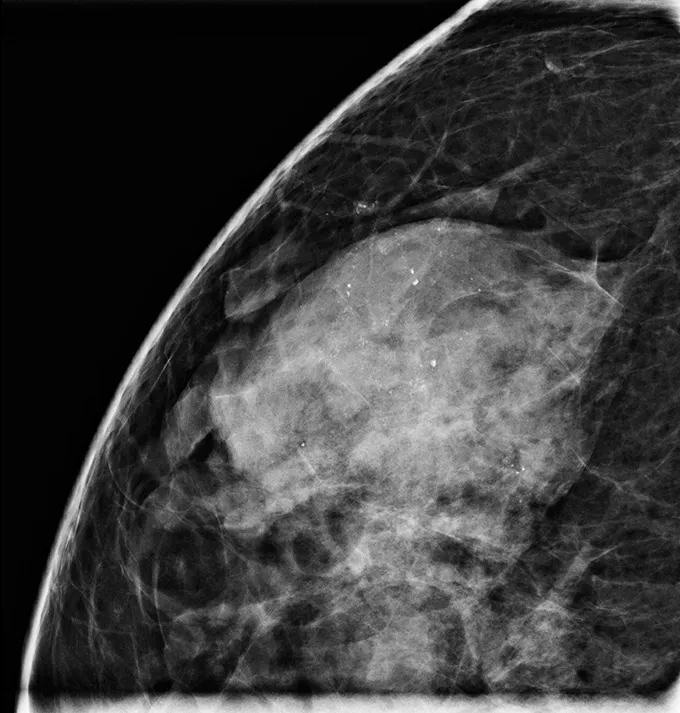

A new study of 957 women evaluated whether it was safe to do active monitoring of a low-risk form of ductal carcinoma in situ, or DCIS — a noninvasive cancer, often called Stage 0 breast cancer, that hasn’t spread beyond the milk ducts — as an alternative to surgery (SN: 8/30/24).

As Hwang notes, the study examined DCIS in women age 40 and over in which abnormal duct cells “did not look particularly aggressive” and that have receptors for hormones such as estrogen or progesterone. Those factors make the cells low risk for becoming invasive cancer and controllable with hormone therapy. About half of the more than 50,000 cases of DCIS diagnosed in the United States each year fall into the low-risk category, Hwang says. People with more aggressive forms of DCIS shouldn’t wait to have it removed, she says.